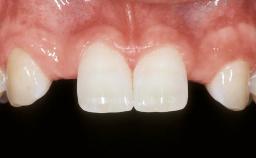

Mauricio Araujo and Flauvia Matarazzo present this straightforward clinical case, demonstrating the potential effect of implant placement depth on the resolution of peri-implant treatment. A 42-year-old systemically healthy female patient, a non-smoker with no history of periodontitis, was treated at the Dental Clinic at the State University of Maringá, Brazil between 2008 and 2009, when she received five implants restored with single crowns at sites 14, 26, 27, 36, and 46. After delivery of the implant-supported prosthetic restorations, the patient was enrolled in the supportive peri-implant therapy (SPiT) maintenance program at the same university.